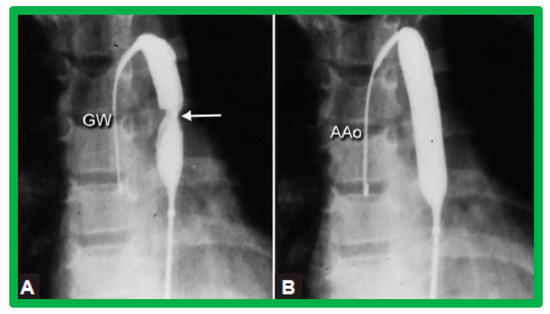

3.3. Aortic Coarctation, Native

3.4. Aortic Coarctation, Postsurgical

4.3. Aortic Coarctation–Native

Revisit BA in the Neonate and Young Infant